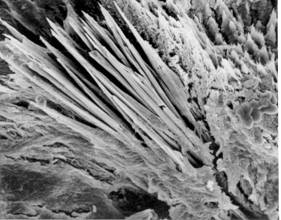

Stébelnaté agregáty močanu sodného,

které se nalézají v krystalizačním jádru whewellitového

kamene. Jádro leží na povrchu v papilární jamce, elektronový mikroskop,

zvětšeno 55x